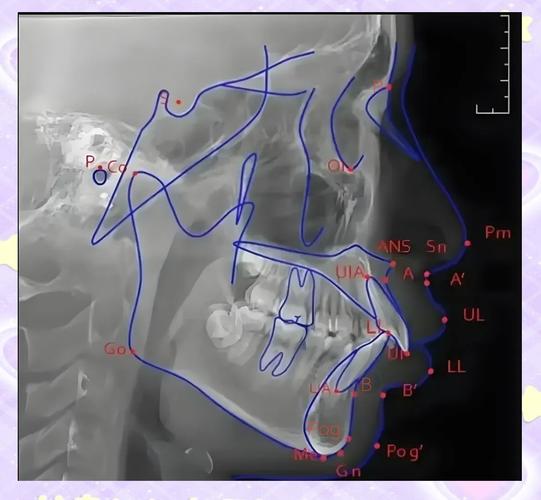

正畸头影测量是口腔正畸学中通过头颅定位X线片对颅颌面结构进行定量分析的重要方法,而标志点的准确定位是头影测量分析的基础,这些标志点代表了颅颌面解剖结构的关键位置,通过它们之间的角度、距离等测量值,可客观评估患者的颌骨形态、牙齿位置、软组织轮廓及生长发育情况,为正畸诊断、治疗方案设计及疗效评价提供科学依据,根据解剖结构的不同,正畸头影测量标志点可分为颅底标志点、上颌标志点、下颌标志点、牙列标志点及软组织标志点五大类,各类标志点均有其特定的定义和临床意义。

蝶鞍点(Sella, S):蝶鞍影像的中心点,即蝶鞍前后径的中点,作为颅测量的基准点,是前颅底平面(SN平面)的后界点,用于确定颅部参考平面的方向,对评估颌骨与颅底的相对位置至关重要。

鼻根点(Nasion, N):鼻额缝的最前点,位于鼻根与额骨的交界处,是前颅底平面(SN平面)的前界点,也是SNA角(上颌相对于颅骨的位置)的关键构成点,对判断上颌骨前后向位置异常(如上颌前突或后缩)有重要意义。

前鼻棘点(Anterior Nasal Spine, ANS):上颌骨前鼻棘的最前点,位于鼻腔底部的硬腭前正中处,代表上颌牙槽突的前部位置,常用于确定上颌平面(ANS-PNS平面)及测量上颌牙槽突的高度。

上齿槽座点(Subspinale, A):上颌牙槽突最前点,通常为ANS点下方上颌骨前壁的凹陷点,是SNA角的构成点之一,直接反映上颌骨前部的相对位置,A点前移提示上颌前突,后移则提示上颌后缩。

翼上颌裂点(Pterygomaxillary Fissure, Ptm):翼上颌裂影像的中心点,代表上颌后部与蝶骨翼突的交界处,用于确定上颌骨的后部位置,常与ANS点构成上颌平面(ANS-Ptm平面),评估上颌骨的长度和倾斜度。

后鼻棘点(Posterior Nasal Spine, PNS):硬腭后部正中棘的最突点,位于软腭附着处的前方,与ANS点共同构成腭平面,反映上颌牙槽突的后部高度,对评估垂直向颌骨关系(如面部高度)有重要价值。

下齿槽座点(Supramentale, B):下颌牙槽突最前点,位于下颌骨前正中,通常在颏嵴上方,是SNB角(下颌相对于颅骨的位置)的构成点,B点位置反映下颌前部的相对位置,B点后移提示下颌后缩,前移则可能为下颌前突。

颏前点(Pogonion, Po):下颌颏部最前点,位于下颌骨颏联合的正前方,代表下颌骨前部的最突点,用于评估下颌整体的前突程度,是面部突度测量的重要标志。

颏下点(Menton, Me):下颌颏部最下点,位于颏联合的下缘,常作为下颌平面的后界点,用于测量下颌支高度、下颌体长度及垂直向面部高度(如全面高)。

下颌角点(Gonion, Go):下颌下缘与下颌支后缘的交角,即下颌角的最凹点,由下颌支 tangent线与下颌体 tangent线的交角构成,反映下颌骨的形态(如下颌角肥大或过小),对评估下颌骨的宽度和垂直向发育有重要意义。

髁突点(Condylion, Cd):髁突后上缘的最突点,代表下颌髁突的位置,部分研究中将其用于评估髁突相对于颅底的位置,对颞下颌关节紊乱的诊断有一定参考价值。

上中切牙点(Upper Incisor, UI):上颌中切牙切缘的最前点或根尖点(根据测量目的选择),用于评估上切牙的突度、倾斜度及唇倾程度,是控制前牙位置的关键指标。

下中切牙点(Lower Incisor, LI):下颌中切牙切缘的最前点或根尖点,反映下切牙的位置,正畸治疗中常通过调整下切牙位置来改善咬合及软侧貌。

软组织鼻根点(Soft Tissue Nasion, Ns):软组织鼻根的最前点,位于鼻额缝软部对应处,反映鼻根部软组织突度,是侧貌轮廓测量的起始点。

上唇突点(Upper Lip, UL):上唇皮肤黏膜交界处的最前点,用于评估上唇突度,与UI点共同构成上唇突度测量(如UL-UI距离),影响侧貌美观。

下唇突点(Lower Lip, LL):下唇皮肤黏膜交界处的最前点,反映下唇位置,与LI点关系密切,正畸治疗中需避免下唇过突或内陷。

颏唇沟点(Soft Tissue Pogonion, Si):下唇与颏部软组织交界处的凹陷点,反映颏唇部形态,是评估侧貌突度的重要指标,颏唇沟深度过浅可能导致“凸面型”外观。